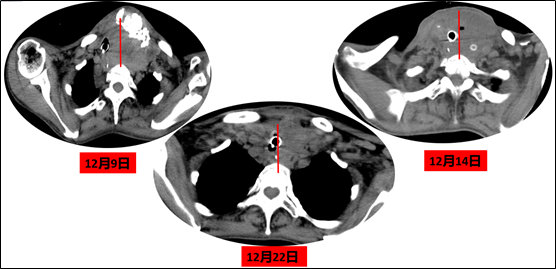

12月16日:病理回报甲状腺低分化癌,可见数个脉管内癌栓。全麻下行右侧甲状腺癌根治术。2次手术后患者气道基本恢复解剖位(图5)。

图5 患者术后胸部CT